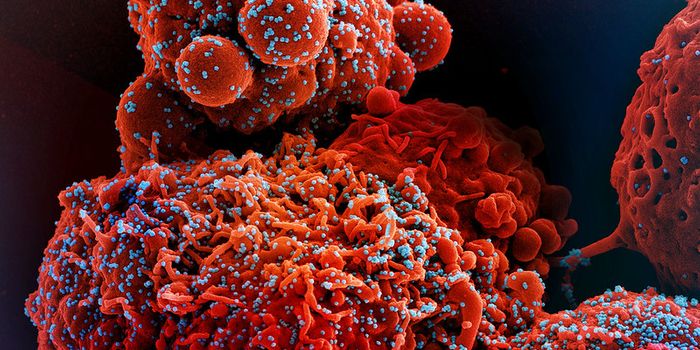

SEP 08, 2024MicrobiologySARS-CoV-2, the pandemic virus that causes COVID-19, has mutated endlessly since it burst on the scene in late 2019. An ...

AUG 27, 2024MicrobiologySince the start of the COVID-19 pandemic, the virus that causes the illness - SARS-CoV-2 - has had a practically infinit ...